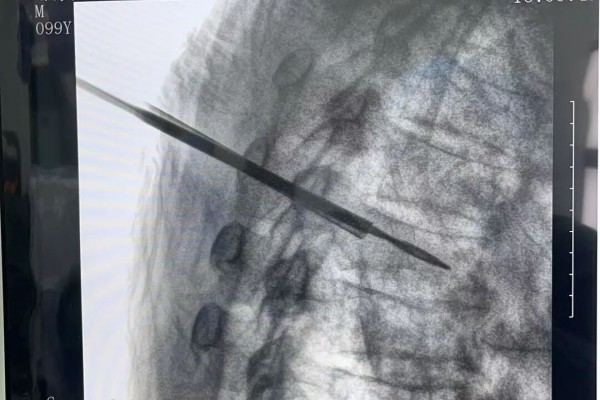

C型臂X光机引导

手术在局部麻醉下进行,在患者背部两侧各开约0.5厘米的小切口,在C型臂X光机引导下,将球囊撑开器精准植入骨折的胸6椎体内。通过球囊缓慢扩张,被压缩的椎体高度得到恢复,随后注入约适量的骨水泥强化椎体。

整个手术过程顺利,手术全程仅耗时约30分钟,出血量极微,骨水泥弥散良好且无渗漏,术后安返病房。在严密的监护下,邬大爷生命体征平稳,未出现任何并发症。